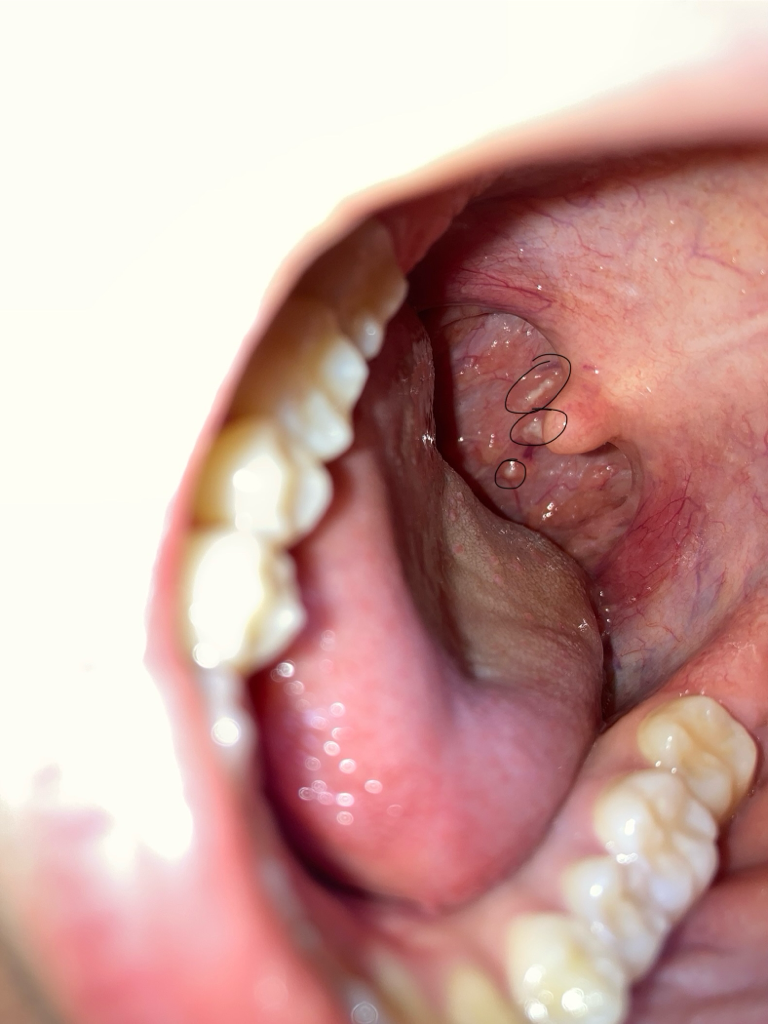

목 안에 하얀게 생겼는데 이게 뭔가요?

우연히 입 안을 봤는데 목에 흰색 뭐가 생겼는데 이게 뭘까요? 아프진않고 느낌도 없어요. 병원 바로 가야하는건가요?......

편도선염이 있는 경우에 생기는 현상입니다. 보통 곱이 끼였다고 하고 exudate 입니다. 편도에서 발생하는 염증현상으로 나타나는 결과물입니다. 이비인후과 방문하여 진찰 받고 처방받는 것을 권유드립니다.